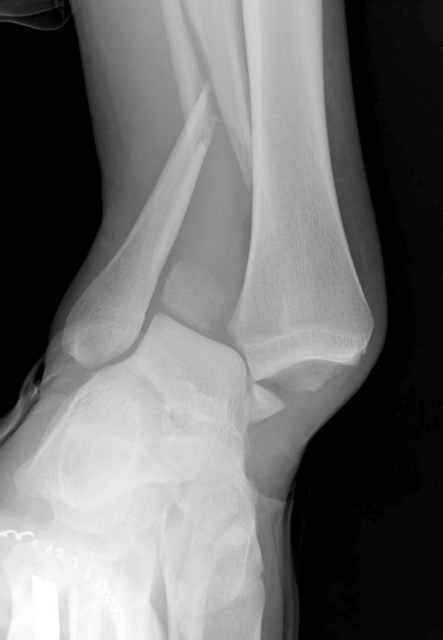

>На сделанных у нас снимках видно, что не все благополучно...

Неравномерность суставной щели может быть связана с разрывом глубокой порции дельтовидной связки и ротацией м/берцовой кости за счет поврежденных структур синдесмоза(репозиция ее на уровне перелома как-будто удовлетворительная).

По моему мнению,ассиметрия суставной щели обусловлена импрессией медиальной части суставной поверхности б/б кости. Да, позиционный винт здесь не лишен, но через 4 недели целесообразность его проведения сомнительна, брейс, ограничение осевой нагрузки достаточно.Есть еще деонтологические аспекты повторной операции, не все так плохо выполнено предыдущим доктором!

Импрессия медиальной части суставной поверхности бывает при супинационном механизме перелома лодыжек (тип А по классификации АО). Здесь механизм пронациия+наружная ротация (тип С, синдесмоз и межкостная мебрана повреждены),

перелом медиальной лодыжки отрывной, при этом в 20-30% бывает повреждение дельтовидной связки.

Клиновидность щели сустава следствие повреждения дельты, невосстановления длины малоберцовой или (хотел сказать "установки в гипсе", но оного, вроде,

нет)? Устранить бы причину. А равно как и тенденцию" к наружному подвывиху. Чрескостный остеосинтез - метод выбора.

Мое мнение, что никакой ротации малоберцовой кости здесь нет и синдесмоз тоже впорядке. Все дело в некачественно репозиции медиального мыщелка. Скорее всего его или немного ротировали при операции или сместили латерально. Более склонен ко второму варианту.

Конечно, компьютерный томограф более информативный метод, но с помощью недорогого обычного стандартного в нейтральном положении стопы: прямого, бокового и косой (ankle mortise) ренгенологического метода можно получить полную информацию о повреждении голеностопного сустава, а сравнительный снимок с другой стороны подтвердить наличие повреждения.

При реконструкции голеностопа, о важности восстановления длины малоберцовой для профилактики пост травматического артроза разбирали в предыдущих дискуссиях. Нарушенную биомеханику голеностопа без восстановления длины малоберцовой, не восстановить только швом медиальной связки.

Расширенная медиальная щель более чем на 4 мм и укорочение малоберцовой более чем 2 мм, а перелом заднего края большеберцовой смещения более 2мм с вовлечением 30% поверхности сустава, считается отходом от нормы голеностопного сустава, и подлежит к оперативному вмещательству.